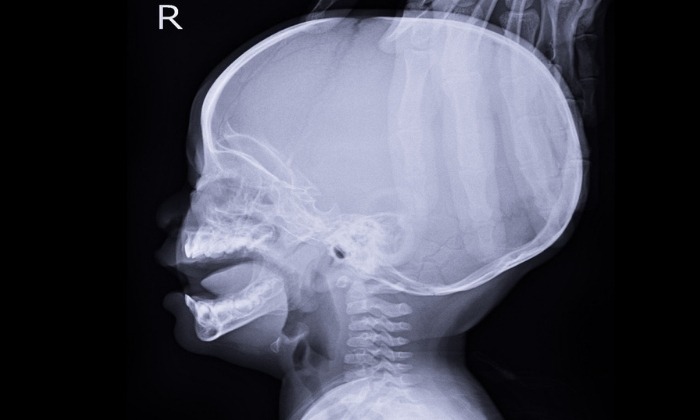

โพรงสมองคั่งน้ำ หรือน้ำคั่งในโพรงสมอง เป็นการที่มีในสมองมีของเหลวส่วนเกิน ที่เพิ่มขนาดของโพรงสมอง และมีแรงกดลงบนสมอง ทำให้ผู้ป่วยมีขนาดหัวโตขึ้น บางทีก็เรียก โรคหัวบาตร

โพรงสมองคั่งน้ำ (Hydrocephalus) หรือ น้ำคั่งในโพรงสมอง หรือน้ำท่วมสมอง เป็นการก่อตัวของของเหลวในโพรงสมอง ของเหลวส่วนเกินเพิ่มขนาดของโพรงสมองและมีแรงกดลงบนสมอง

- ศีรษะใหญ่ผิดปกติ

- ขนาดศีรษะใหญ่ขึ้นอย่างรวดเร็ว

หากคุณสงสัยว่า คุณหรือลูกของคุณมีภาวะโพรงสมองคั่งน้ำ แพทย์จะทำการตรวจร่างกายเพื่อตรวจหาสิ่งบ่งชี้หรืออาการ ในเด็กนั้น แพทย์จะตรวจดวงตาที่โบ๋ลึก ปฏิกิริยาตอบสนองช้า ขม่อมนูน และขนาดศีรษะที่ใหญ่กว่าปกติสำหรับช่วงอายุนี้

การตรวจหน้าอกด้วยเครื่องเอกซเรย์คอมพิวเตอร์ (CT) ยังสามารถช่วยวินิจฉัยภาวะโพรงสมองคั่งน้ำได้ในเด็กและผู้ใหญ่ การตรวจด้วยวิธี CT scan ใช้คลื่นเอกซเรย์ต่างๆ เพื่อสร้างภาพถ่ายของสมองตามแนวขวาง การตรวจด้วยวิธีนี้สามารถแสดงให้เห็นถึงโพรงสมองที่ขยายตัว ที่เกิดจาก ภาวะน้ำหล่อเลี้ยงสมองและไขสันหลังมากเกินไป